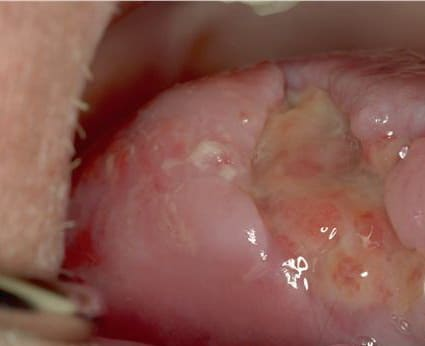

Pemphigis Vulgaris =الفقاع الشائع